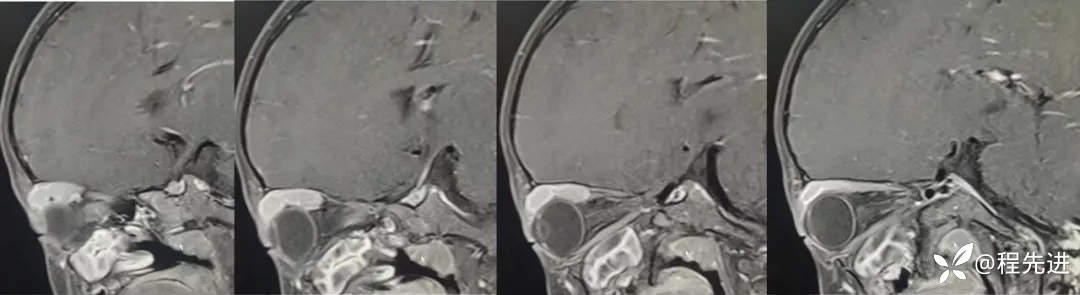

MRI平扫+增强:

T1增强: